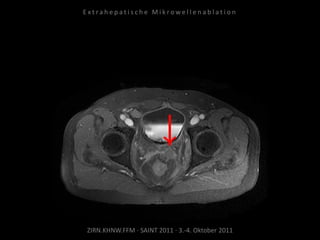

Kontrollbildgebung:

MRT 10.09.2010

Verlaufskontrolle:

MRT 09.06.2011

MRT 10.08.2011

CT 15.08.2011

Keine weitere Tumorvitalität.